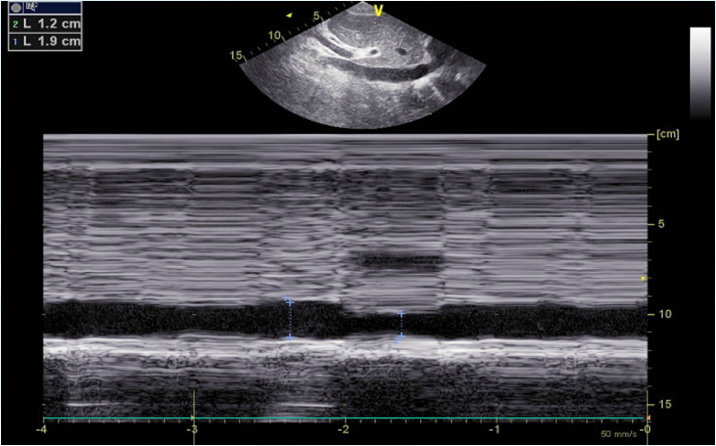

超声容量评估

剑突下切面下腔静脉直径1219 mm(图2)

2  超声容量评估